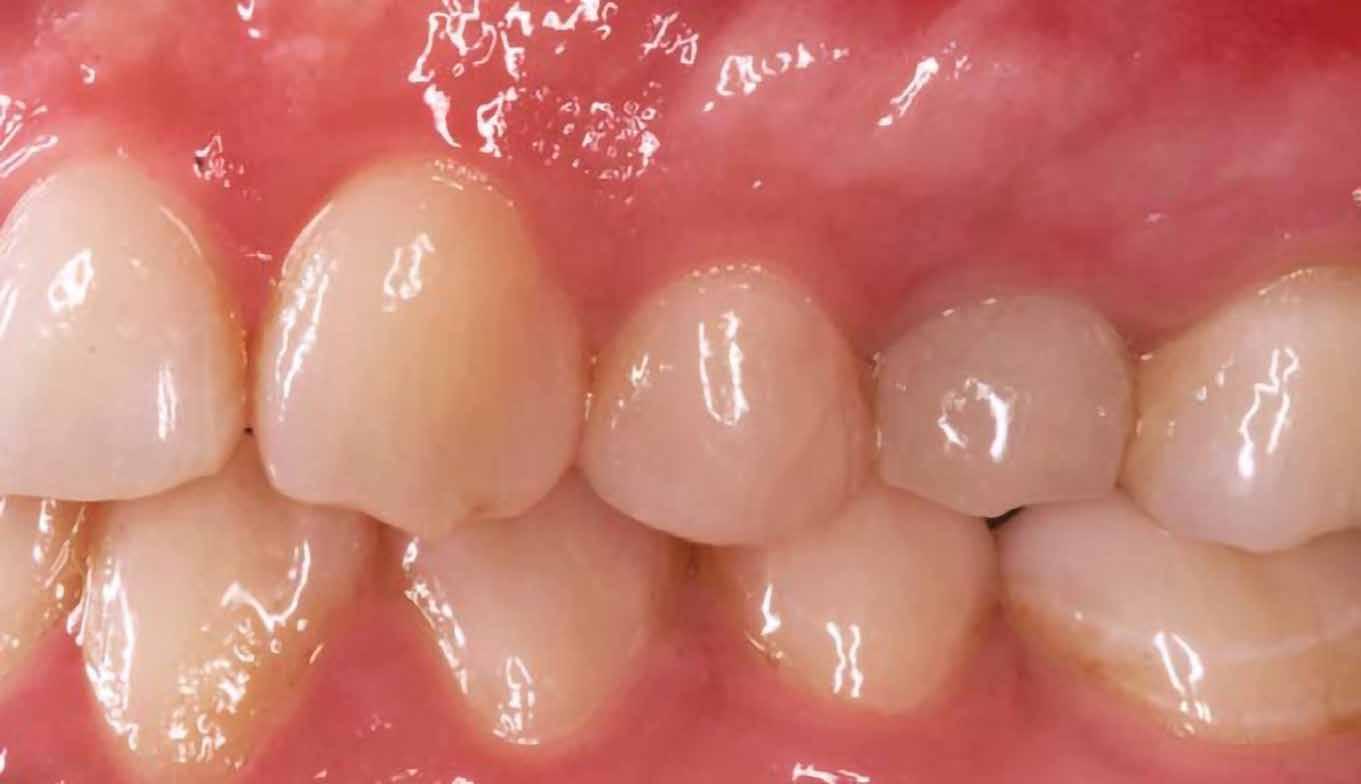

16. ábra: Klinikai kép az implantátumok körüli lágyszövetről a végleges pótlásátadás után. – 17. ábra: Klinikai kép az implantátumok körüli lágyszövetről egy évvel az átadást követően. – 18. ábra: Klinikai kép az implantátumok körüli lágyszövetről két évvel az átadást követően. – 19. ábra: Klinikai kép az implantátumok körüli lágyszövetről öt évvel az átadást követően.

lási csavarokat (PEEK titáncsavarral) maximum 15 Ncm-rel húztuk meg (3–6. ábra). Az összes implantátum kiváló stabilitást mutatott (a mérésekhez Periotestet használtunk, a Medizintechnik Gulden jóvoltából), és teljesen osszeointegrálódott. Ezt a radiológiai vizsgálatok is megerősítették.

tottuk (az okklúziós koncepciók alapján az implantációs pótlások nem voltak vezető fogak, és csak könnyű érintkezéseket alakítottunk ki, amelyeket artikulációs papírral ellenőriztünk). A páciensek instrukciókat kaptak a megfelelő szájhigiénére vonatkozóan, összpontosítva a fogköz kefékkel történő tisztítására. Végső kontroll röntgenfelvétel készült. A PEEK felépítmény nem radioopák, így az implantátum és a korona közötti távolság könnyen meghatározható a röntgenfelvételen: a felépítmény megfelelően illeszkedik az implantátumban, ha az implantátum válla és a korona alsó széle közötti rés 0,55 mm a röntgenfelvételen (8–11. ábra)

Minden páciens elégedett volt a kezelés eredményével, a funkcionális és az esztétikai eredmény egyaránt kielégítő volt. Az egyetlen megjegyzés – a teljes kezelés hosszú időtartama – a felső állkapocs esetében volt. A meghosszabbított, öt hónapos csontintegrációs periódus miatt, a teljes

eljárás több mint hat hónapig tartott. A kezelő szemszögéből a gyártó szigorú előírásainak betartása mellett nem volt jelentős különbség a titánimplantátumok használatához képest. A felső és alsó állcsont fogainak pótlásában a CERALOG implantátumok megfelelő és stabil alternatívának tűnnek a titánimplantátumokkal szemben.